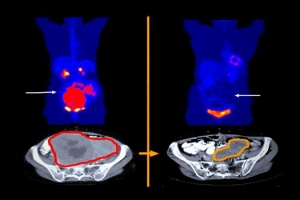

진단 어려워 치료 늦은 기스트, 이제 암세포만 콕 찍어 공략한다